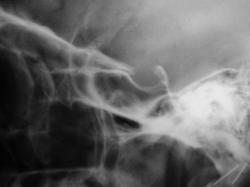

Как следует расценить "тень" на фоне клиновидной (основной) пазухи.

Наверное, сфеноидит. Похоже, что клиновидная пазуха разделена сагиттальной костной перегородкой на две неравные части. Пневматизация бОльшей правой половины не нарушена. А левой - снижена. Вероятно, эта левая часть пазухи и дает неравномерное снижение пневматизации на боковой рентгенограмме. В любом случае, если у пациента головные боли, то вероятность сфеноидита ещё выше (неврологи, кстати, не всегда вспоминают про сфеноидит, когда пользуют пациентов с головной болью). А чтобы сфеноидит доказать без КТ, надо снять околоносовые пазухи с открытым ртом (извините за банальные рекомендации).